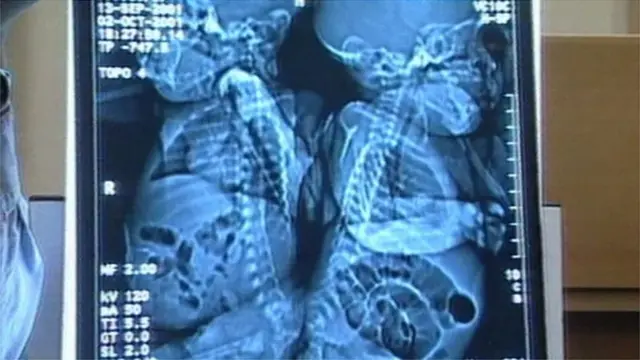

ڈاکٹر بتاتے ہیں کہ آپریشن تھیٹر میں کچھ دیر کے لیے تو عملے کی سانسیں اوپر نیچے ہوئی تھیں لیکن پھر جلد ہی تھیٹر میں تالیاں گونج اٹھیں۔ 16 گھنٹے کے تھکا دینے والے آپریشن کے بعد آخر کار ان بچیوں کو الگ کر دیا گیا جن کی ریڑھ کی ہڈی تین ماہ سے ایک دوسرے سے جڑی ہوئی تھی۔

برمنگھم کے بچوں کے ہسپتال میں یہ ایک تاریخی دن تھا کیونکہ یہ برطانیہ میں اپنی نوعیت کا پہلا آپریشن تھا اور دنیا بھر میں ایسا آپریشن تیسری مرتبہ کیا جا رہا تھا۔ یہ ایک انتہائی خطرناک آپریشن تھا کیونکہ آپس میں جُڑے ہوئے جڑواں بچوں میں آپریشن کے بعد زندہ بچ جانے کا تناسب پانچ فیصد سے لے کر 25 فیصد تک ہوتا ہے۔

اگر ان بہنوں کو آپریشن کے ذریعے کامیابی سے الگ کر بھی لیا جاتا، تو بھی اس بات کا خطرہ بہت زیادہ تھا کہ جب ڈاکٹر دونوں کو کمر سے کاٹ کر الگ کریں گے تو ان میں سے ایک یا دونوں کو فالج ہو سکتا تھا۔

سانچیا اور ایمان کو جس آپریشن کی ضرورت تھی وہ پہلے کبھی برطانیہ میں نہیں کیا گیا تھا۔ اس میں ان کی ریڑھ کی ہڈی کو دو حصوں میں تقسیم کرنا تھا جو نیچے سے جڑی ہوئی تھی۔

ڈاکٹروں نے جن کی قیادت نیورو سرجن ٹونی ہاکلے کر رہے تھے، ریڑھ کی ہڈی کو تقسیم کیا اور کچھ اہم حصوں کو بھی علیحدہ کیا، جن میں مثانے بھی شامل تھے۔

اس آپریشن کے متعلق گارڈیئن اخبار سے بات کرتے ہوئے ٹونی ہاکلے نے کہا: 'وہ دونوں اکٹھی آئیں اور ایک ہو گئیں۔ وہ ایک ڈگری گھومی بھی تھیں۔ ہمیں اس طرح کاٹنا تھا کہ ہر لڑکی کو ریڑھ کی ہڈی بھی ملتی، اور اسے ڈھانپنے کے لیے ٹیوب بھی بنانا تھی۔

'کاٹنے کی تکنیک روایتی تھی لیکن اہم یہ تھا کہ کہاں سے کاٹنا ہے۔ ہمارے پاس مدد کے لیے نیورو سٹیمولیٹرز تھے۔'

ریڑھ کی ہڈی کی علیحدگی کے بعد، بچوں کے سرجن پیٹر گورنال اور جڑے ہوئے بچوں کے دنیا کے سب سے سرکردہ ماہرین میں سے ایک، گریٹ اورمونڈ سٹریٹ ہسپتال کے لیوس سپٹز نے بہت احتیاط سے لڑکیوں کے اعضا نکالنے شروع کر دیے، جو کہ مکمل تھے لیکن وہاں پھنس چکے تھے۔